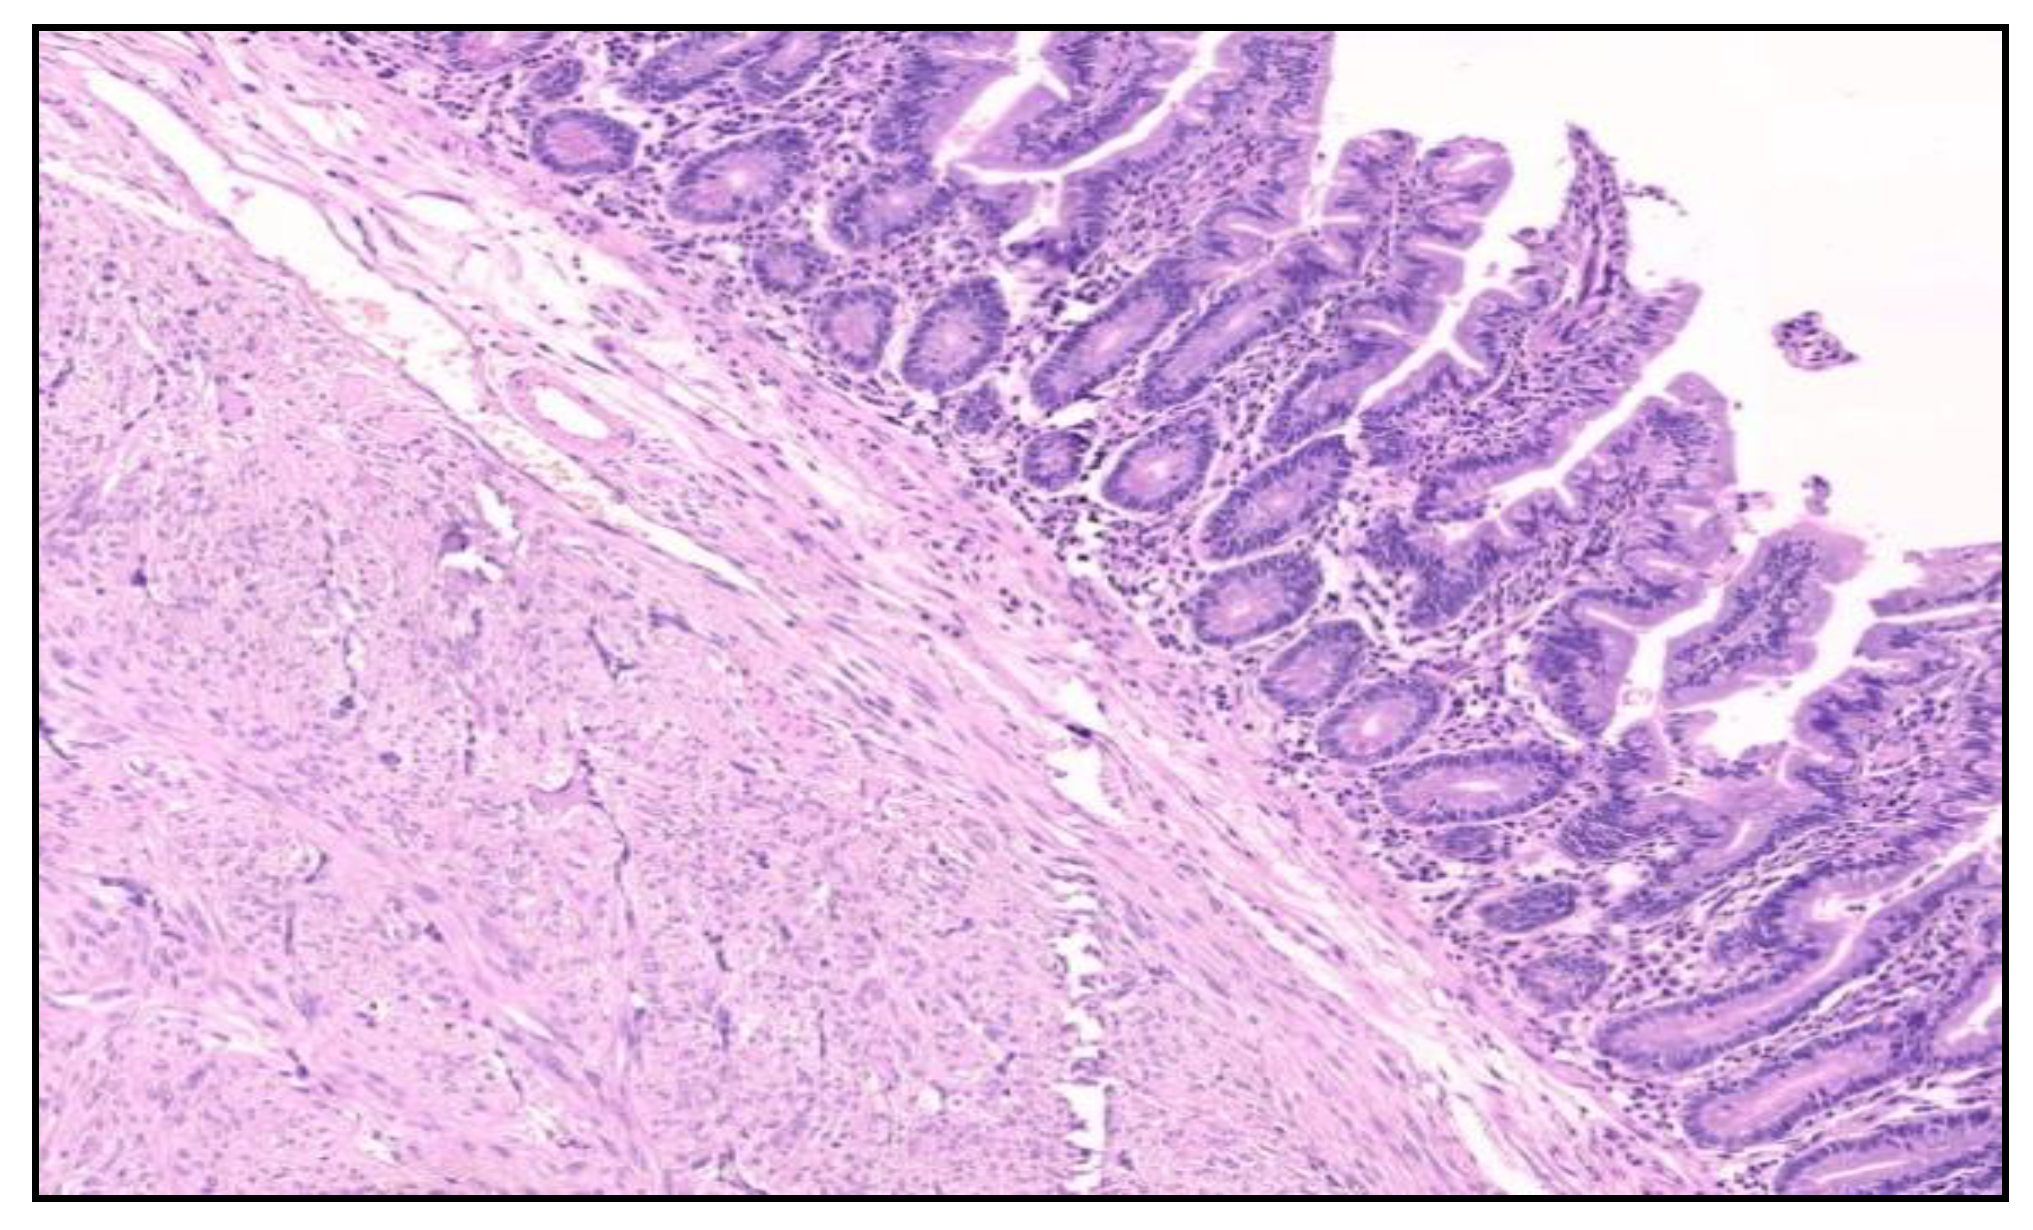

The histological examination of the specimen demonstrated an intramural small tumor −2 cm in diameter with intraluminal growth and obstruction. The final diagnosis was a high-grade ulcerated GIST with classic spindle cells, clear resection margins and no lymph node invasion (Figure 4). Mitotic activity was 12/50 on HPF (High-Power Fields). Ki67 proliferation marker labels 10% of the nuclei (Figure 5).

Figure 4.

Microscopic finding bundles of spindle cells with elongated nuclei and significant mitotic activity (H & E staining; 100x optical magnification).